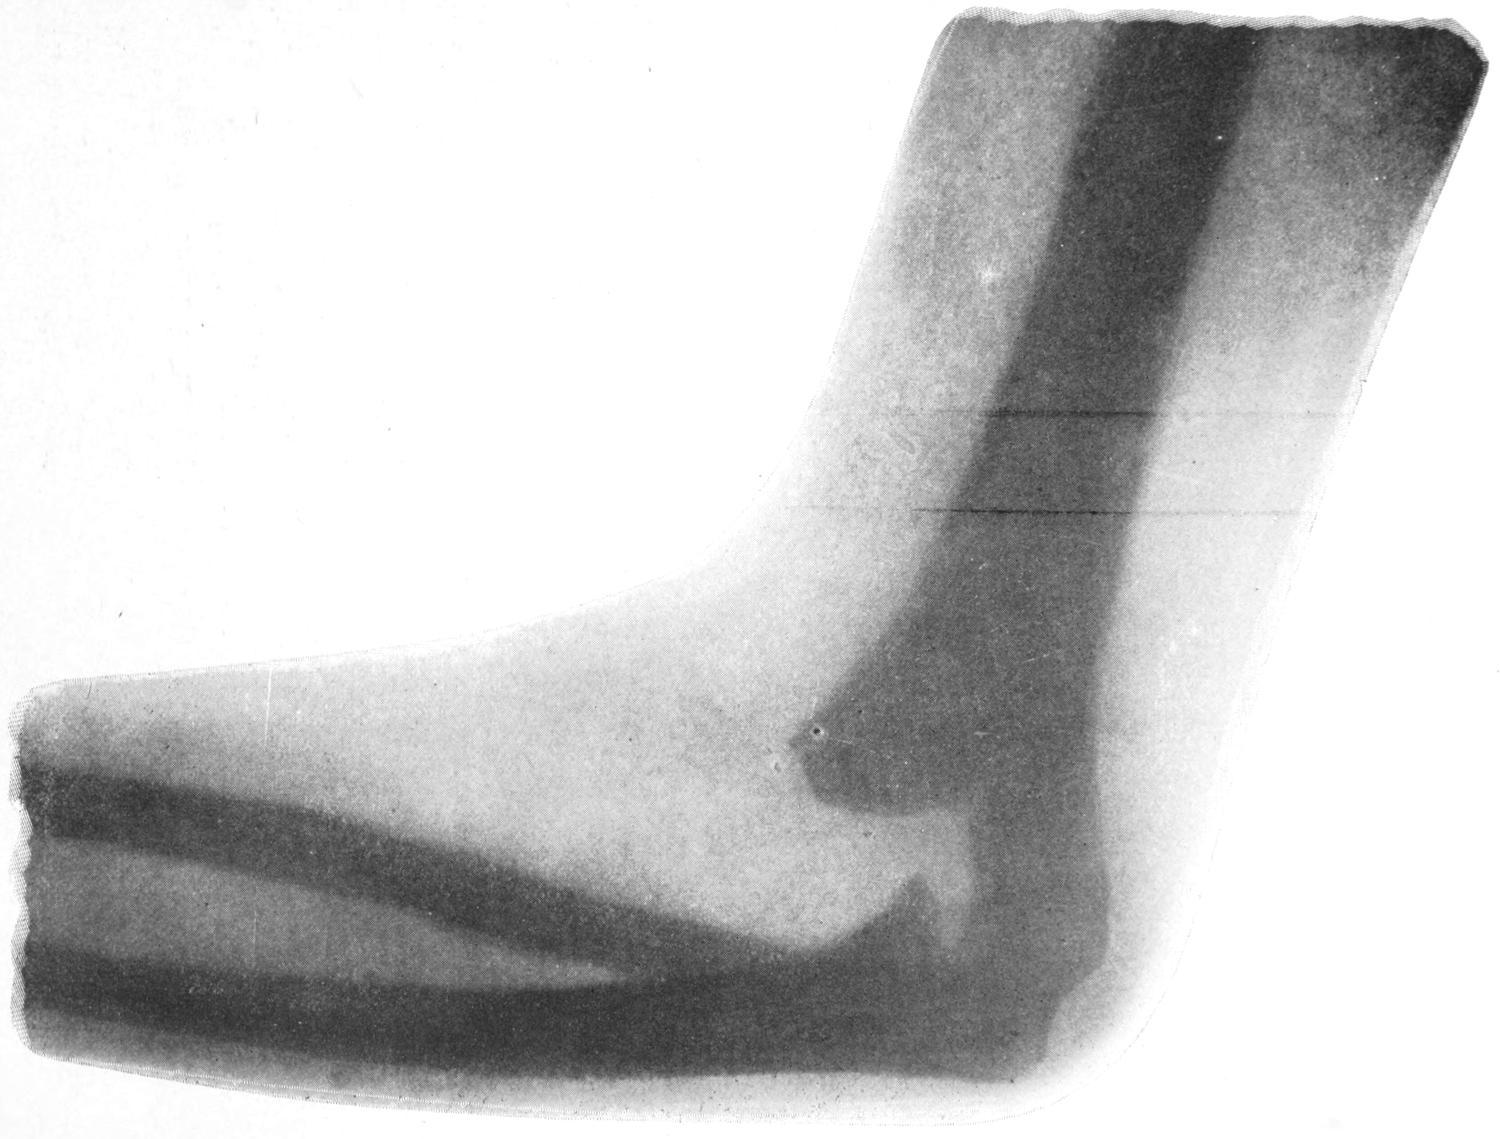

Waller’s experiment of placing a freezing mixture over the ulnar nerve at the back of the elbow is also significant, the result being congestion and elevation of surface temperature of the fingers supplied by this nerve. Congestion and swelling have also been observed after fracture of the internal condyle of the humerus, by which this nerve was pressed upon; and similar phenomena may be noted in fingers or toes as the result of injuries of other nerves.